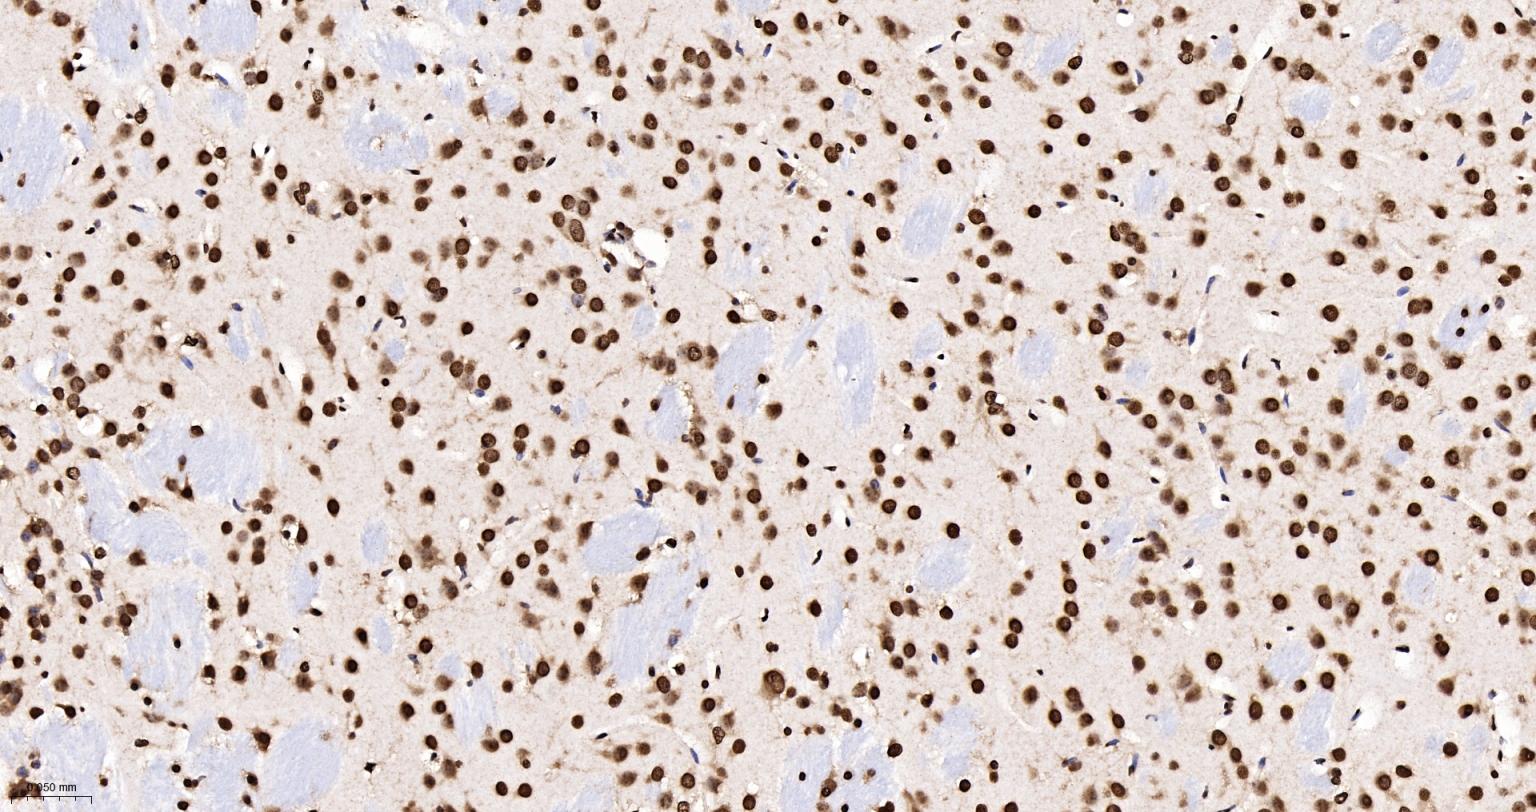

Paraformaldehyde-fixed, paraffin embedded Human Cerebrum; Antigen retrieval by boiling in sodium citrate buffer (pH6.0) for 15 min; The section was incubated with hnRNP K Monoclonal Antibody, Unconjugated (bsm-61246R) at 1:200 overnight at 4°C, followed by conjugation to the bs-0295G-HRP and DAB (C-0010) staining.